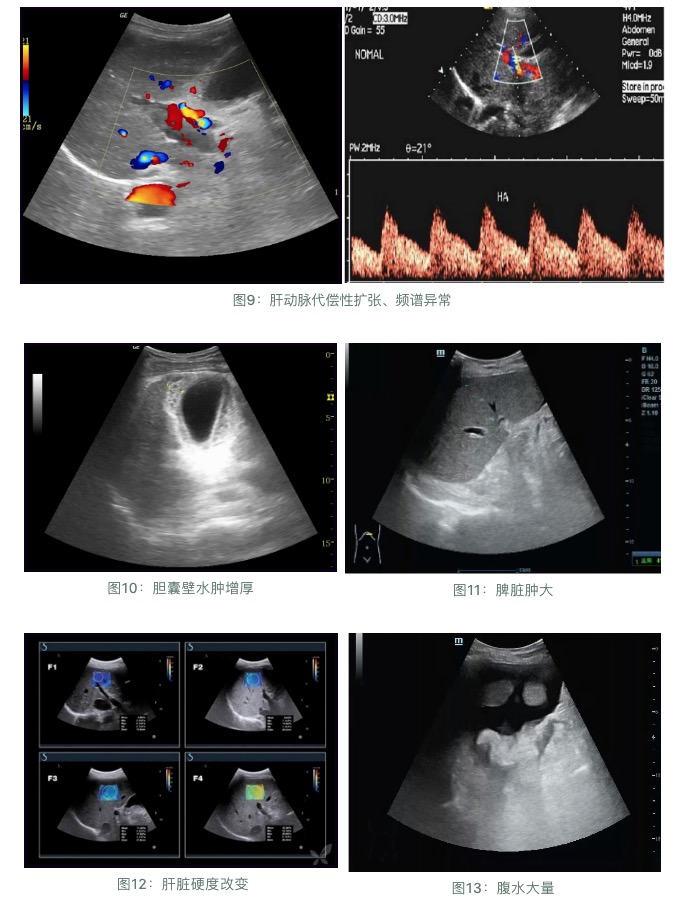

超聲檢查:

肝臟受病毒感染和發(fā)生炎癥后,就會造成肝臟內(nèi)部的結(jié)構(gòu)損傷,從局部的纖維化、結(jié)節(jié)性肝硬化到最后的全面硬化,超聲檢查是早期發(fā)現(xiàn)肝硬化的最直接指標(biāo)。

肝臟彈性檢查、肝穿刺病理學(xué)檢查等等。